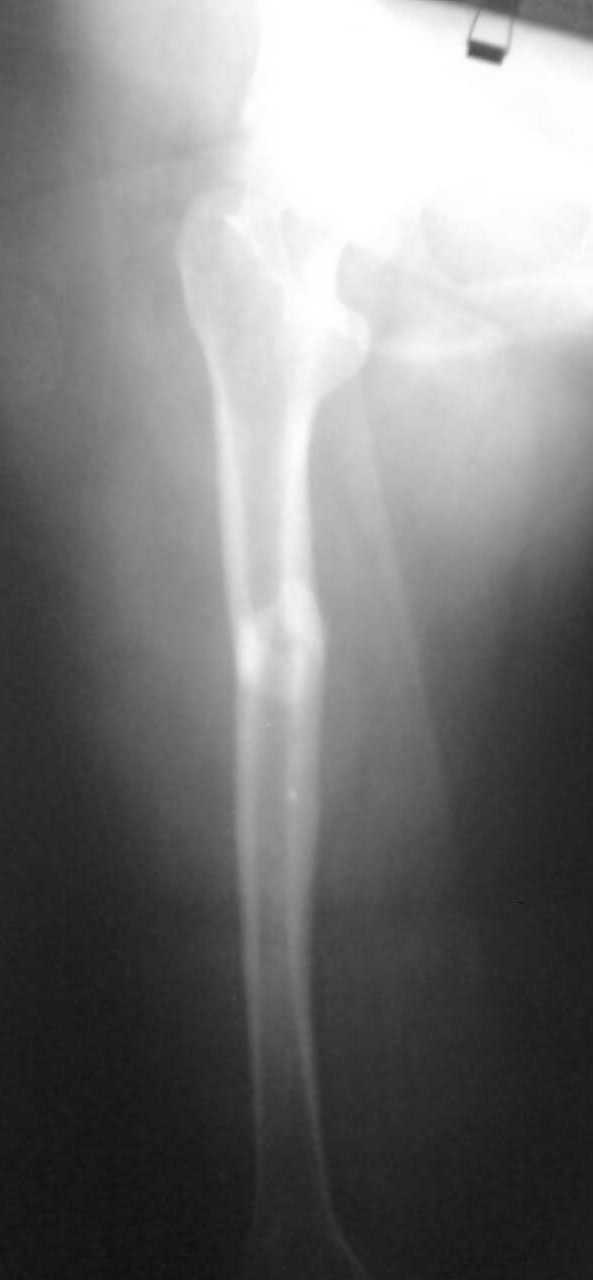

Re: перелом бедренной кости

Перелом поперечный с незначительным смещением и с захождением отломков около 2,0см. Перелом типа А 1.